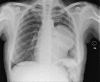

Giant thoracic mass: an unusual presentation of primary pulmonary Hodgkin's lymphoma

Primary pulmonary Hodgkin's lymphoma (PPHL) is rare. PPHL without peripheral lymphadenopathy or hepatosplenomegaly is exceptionally uncommon. We present a 61-year-old woman believed to have a solitary intrapulmonary fibrous tumour on a CT and a CT-guided biopsy, until surgical excision. Histopathology and immunohistochemistry of the excised mass confirmed PPHL. PPHL is a very rare differential diagnosis of large solitary intrapulmonary masses. A CT-guided biopsy is recommended, as it can be diagnostic, reserving excision for cases where the diagnosis remains in doubt.